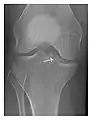

Occult osseous injuries may result from a direct blow to the bone by compressive forces of adjacent bones against one another or by traction forces during an avulsion injury. Lesions in the tibial plateau, hip, ankle, and wrist are often missed. In a tibial plateau fracture, any disruption of the posterior and anterior cortical rims of the plateau should be sought. Impaction of subchondral bone will appear as an increased sclerosis of the subchondral bone (Figure 1). In the hip, posterior acetabular fractures also present subtle radiographic findings. The acetabular lines should then be carefully examined keeping in mind that the posterior rim, which is harder to see on X-rays, is more frequently fractured than the anterior rim (Figure 2). In the wrist, detection of carpal bone fractures is often challenging, with up to 18% of scaphoid fractures radiographically occult. Carpal fractures, especially the scaphoid, are associated with the risk of avascular necrosis. In apparently normal wrist radiographs from symptomatic patients, if there is history of a fall on an outstretched hand with pain in the anatomic snuffbox, suggesting scaphoid injury, the initial examination with posteroanterior, lateral, and pronation oblique views must be complemented by other specific views such as supination oblique and the "scaphoid" view A careful examination of cortices for evidence of discontinuity or offset and cancellous bone for lucency is necessary (Figure 3).[1]

a

b

c

Figure 1: A 56-year-old woman presenting with left knee pain after a fall. (a) Initial anteroposterior radiograph was considered normal, however, subtle cortical disruption of the anterior rim of the medial tibial plateau, medial to the tibial spine, is noted (arrow). (b) Coronal T1-weighted MRI confirms the cortical disruption (arrow) and shows extensive fracture through the proximal tibia. (c) Coronal proton density-weighted image with fat saturation shows extensive edema in the subchondral bone. Note also hypersignal adjacent to the medial collateral ligament corresponding to a grade I sprain (arrowheads).[1]